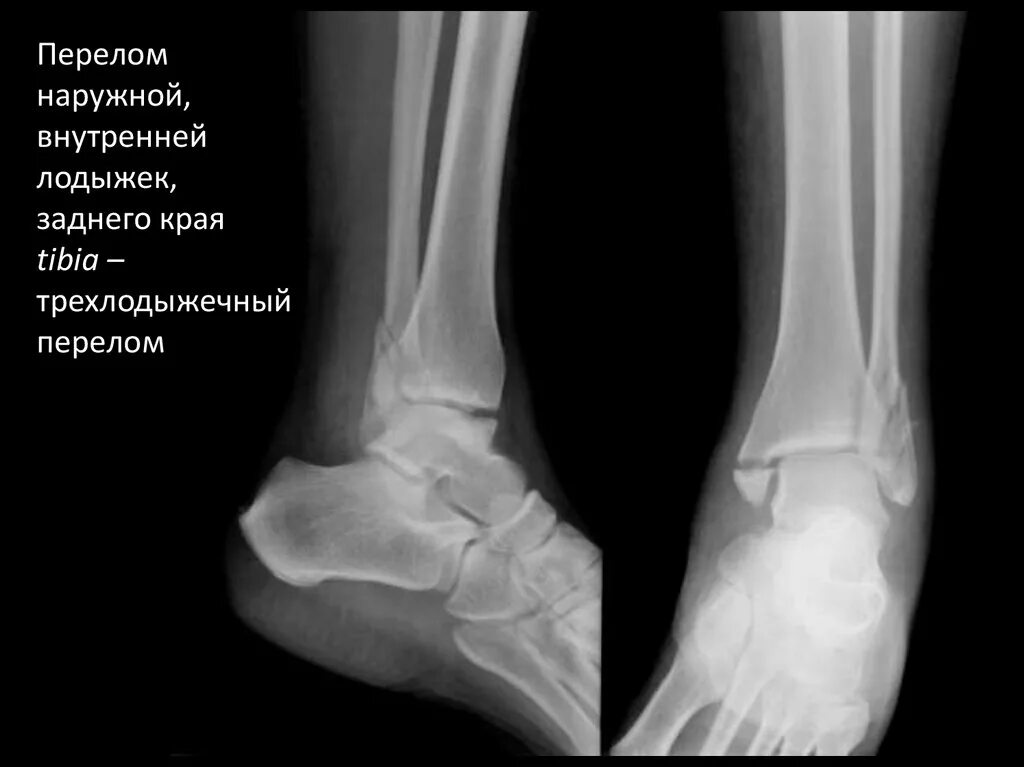

Смещение сустава стопы